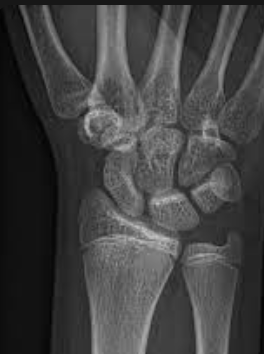

radiocarpal joint

Bones that articulate:radius scaphoid and lunate

Joint type: condyle synovial joint

\

wrist

Radiocarpal joint type: condyloid synovial joint

Intercarpal joint type: synovial plane joints

Carpometacarpal joint type(s): synovial plane joints